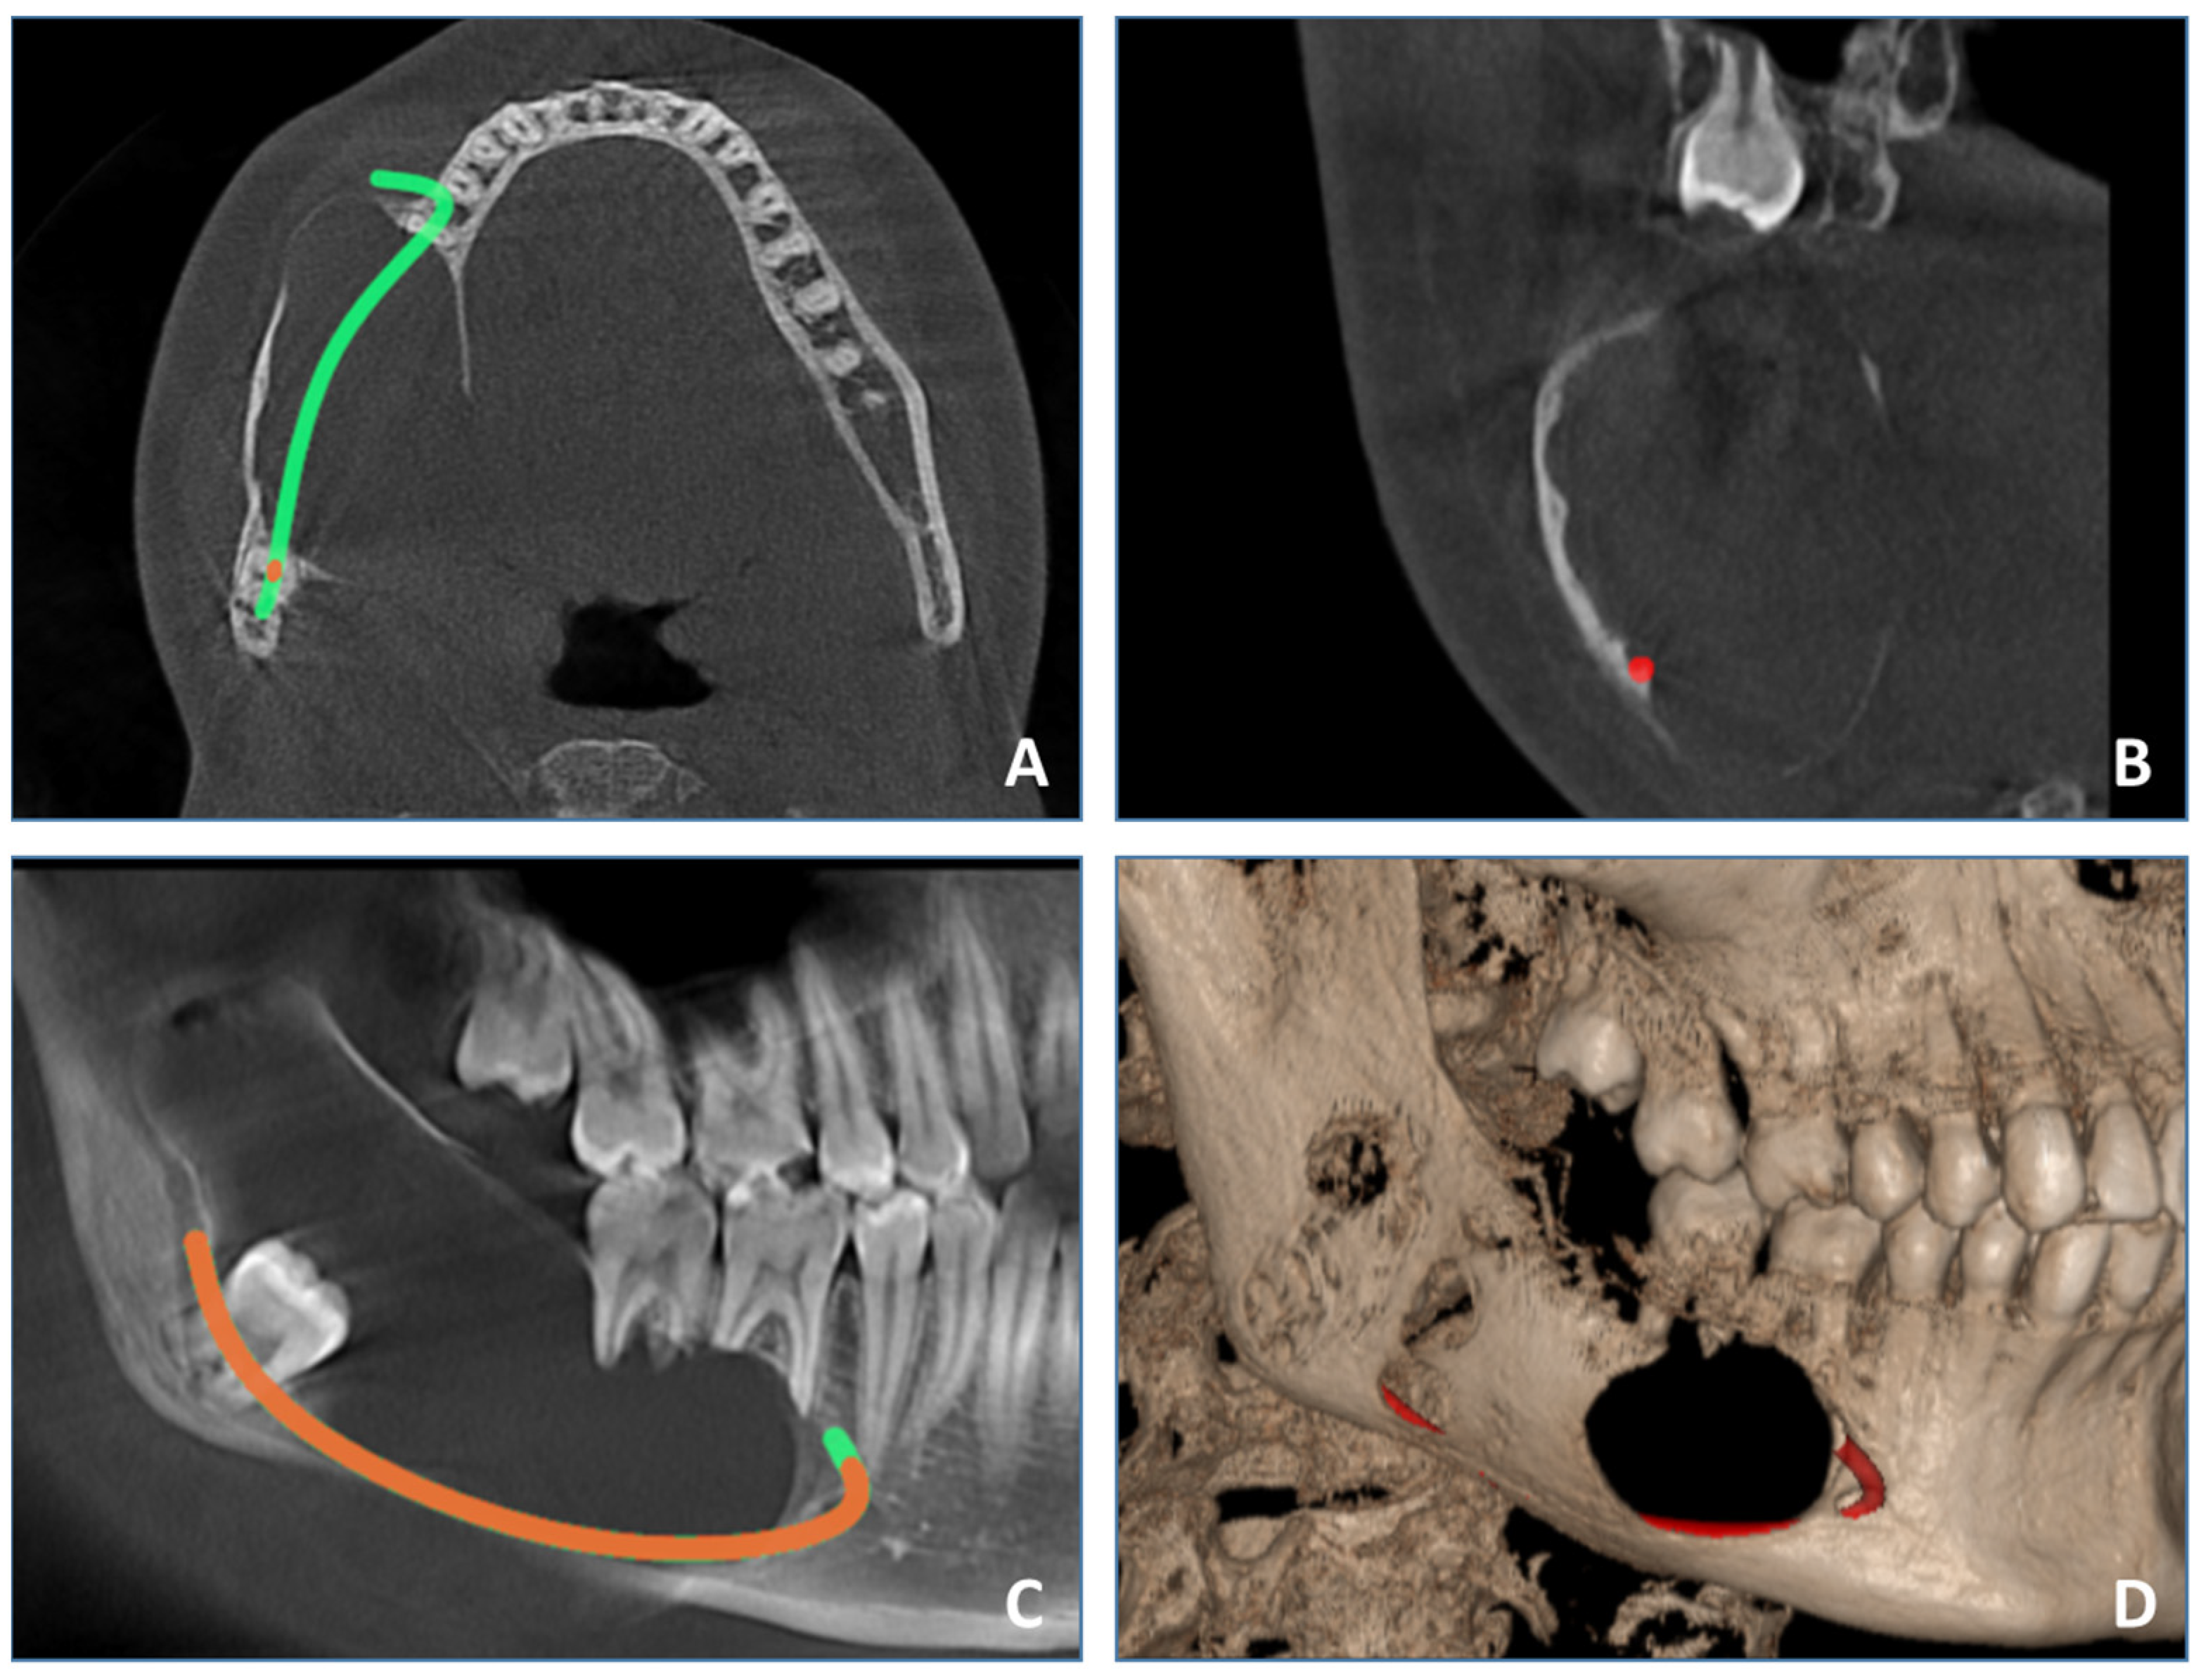

The patient underwent cone beam computed tomography (CBCT), which provides a detailed 3D analysis of the dentition and cortical and medullary bone free of superimpositions compared with classic radiographs like OPG. Compared with other cross-sectional imaging modalities like spiral computed tomography or MRI, it is easily available, relatively inexpensive and generally has a lower radiation dose. CBCT examination (Figure 3) revealed a well-defined expansive radiolucency involving the right mandible, measuring approximately 64 mm/25 mm/26 mm centimeters (sagittal/transversal/vertical). The lesion spans in the sagittal plane from the periapical region of the first right mandibular molar, involving the body, angle and ramus, to the sigmoid notch, vertically from the crest of the mandibular ridge to the lower border of the mandible. Bucco-lingual expansion was noted with extensive thinning of cortical plates and perforation of cortical plates. Displacement of impacted lower right third molar inferiorly into the lower border of the mandibular angle was observed. Resorption of the roots of the first and second right mandibular molars was noted. The inferior alveolar nerve canal was displaced inferiorly.

Figure 3. CBCT examination. (A)—axial view, (B)—coronal view, (C)—sagittal view, (D)—3D reconstruction.